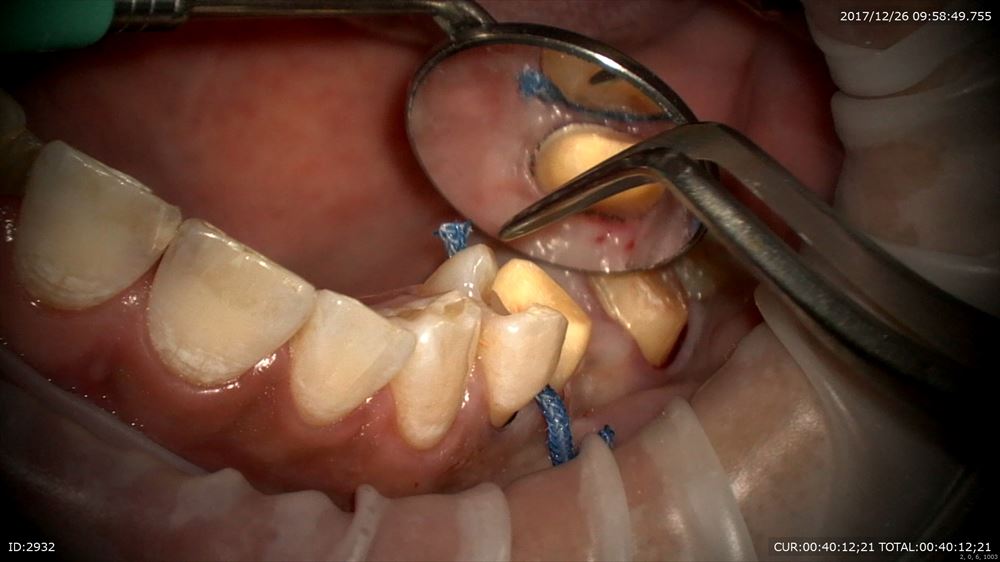

次の患者さまは過去に歯周病治療をした患者さまのメンテナンス。メンテナンスは衛生士だけの仕事ではありません。私も行います。無痛で行います。

綺麗になりました。歯ブラシいつも完璧でありがとうございます!!歯科医がメンテナンスを行うメリットは沢山あります。私は行います。ツルツルになりました。